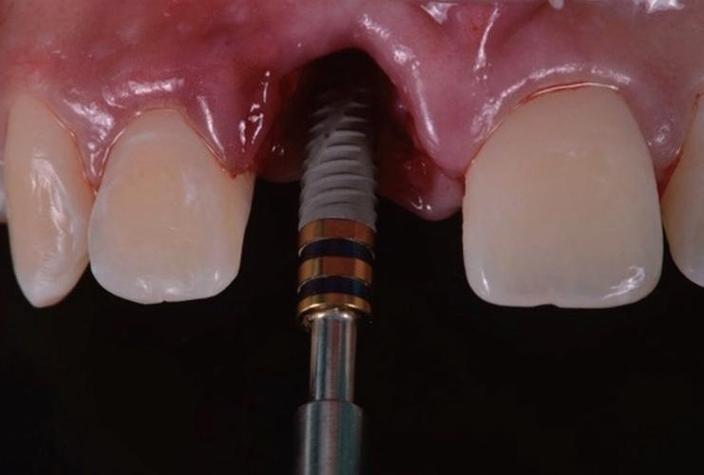

- 即刻手术:局部麻醉下拔除患牙,同期将种植体(如钛合金材质)植入牙槽骨,通过基台连接临时牙冠,即刻恢复牙齿形态;